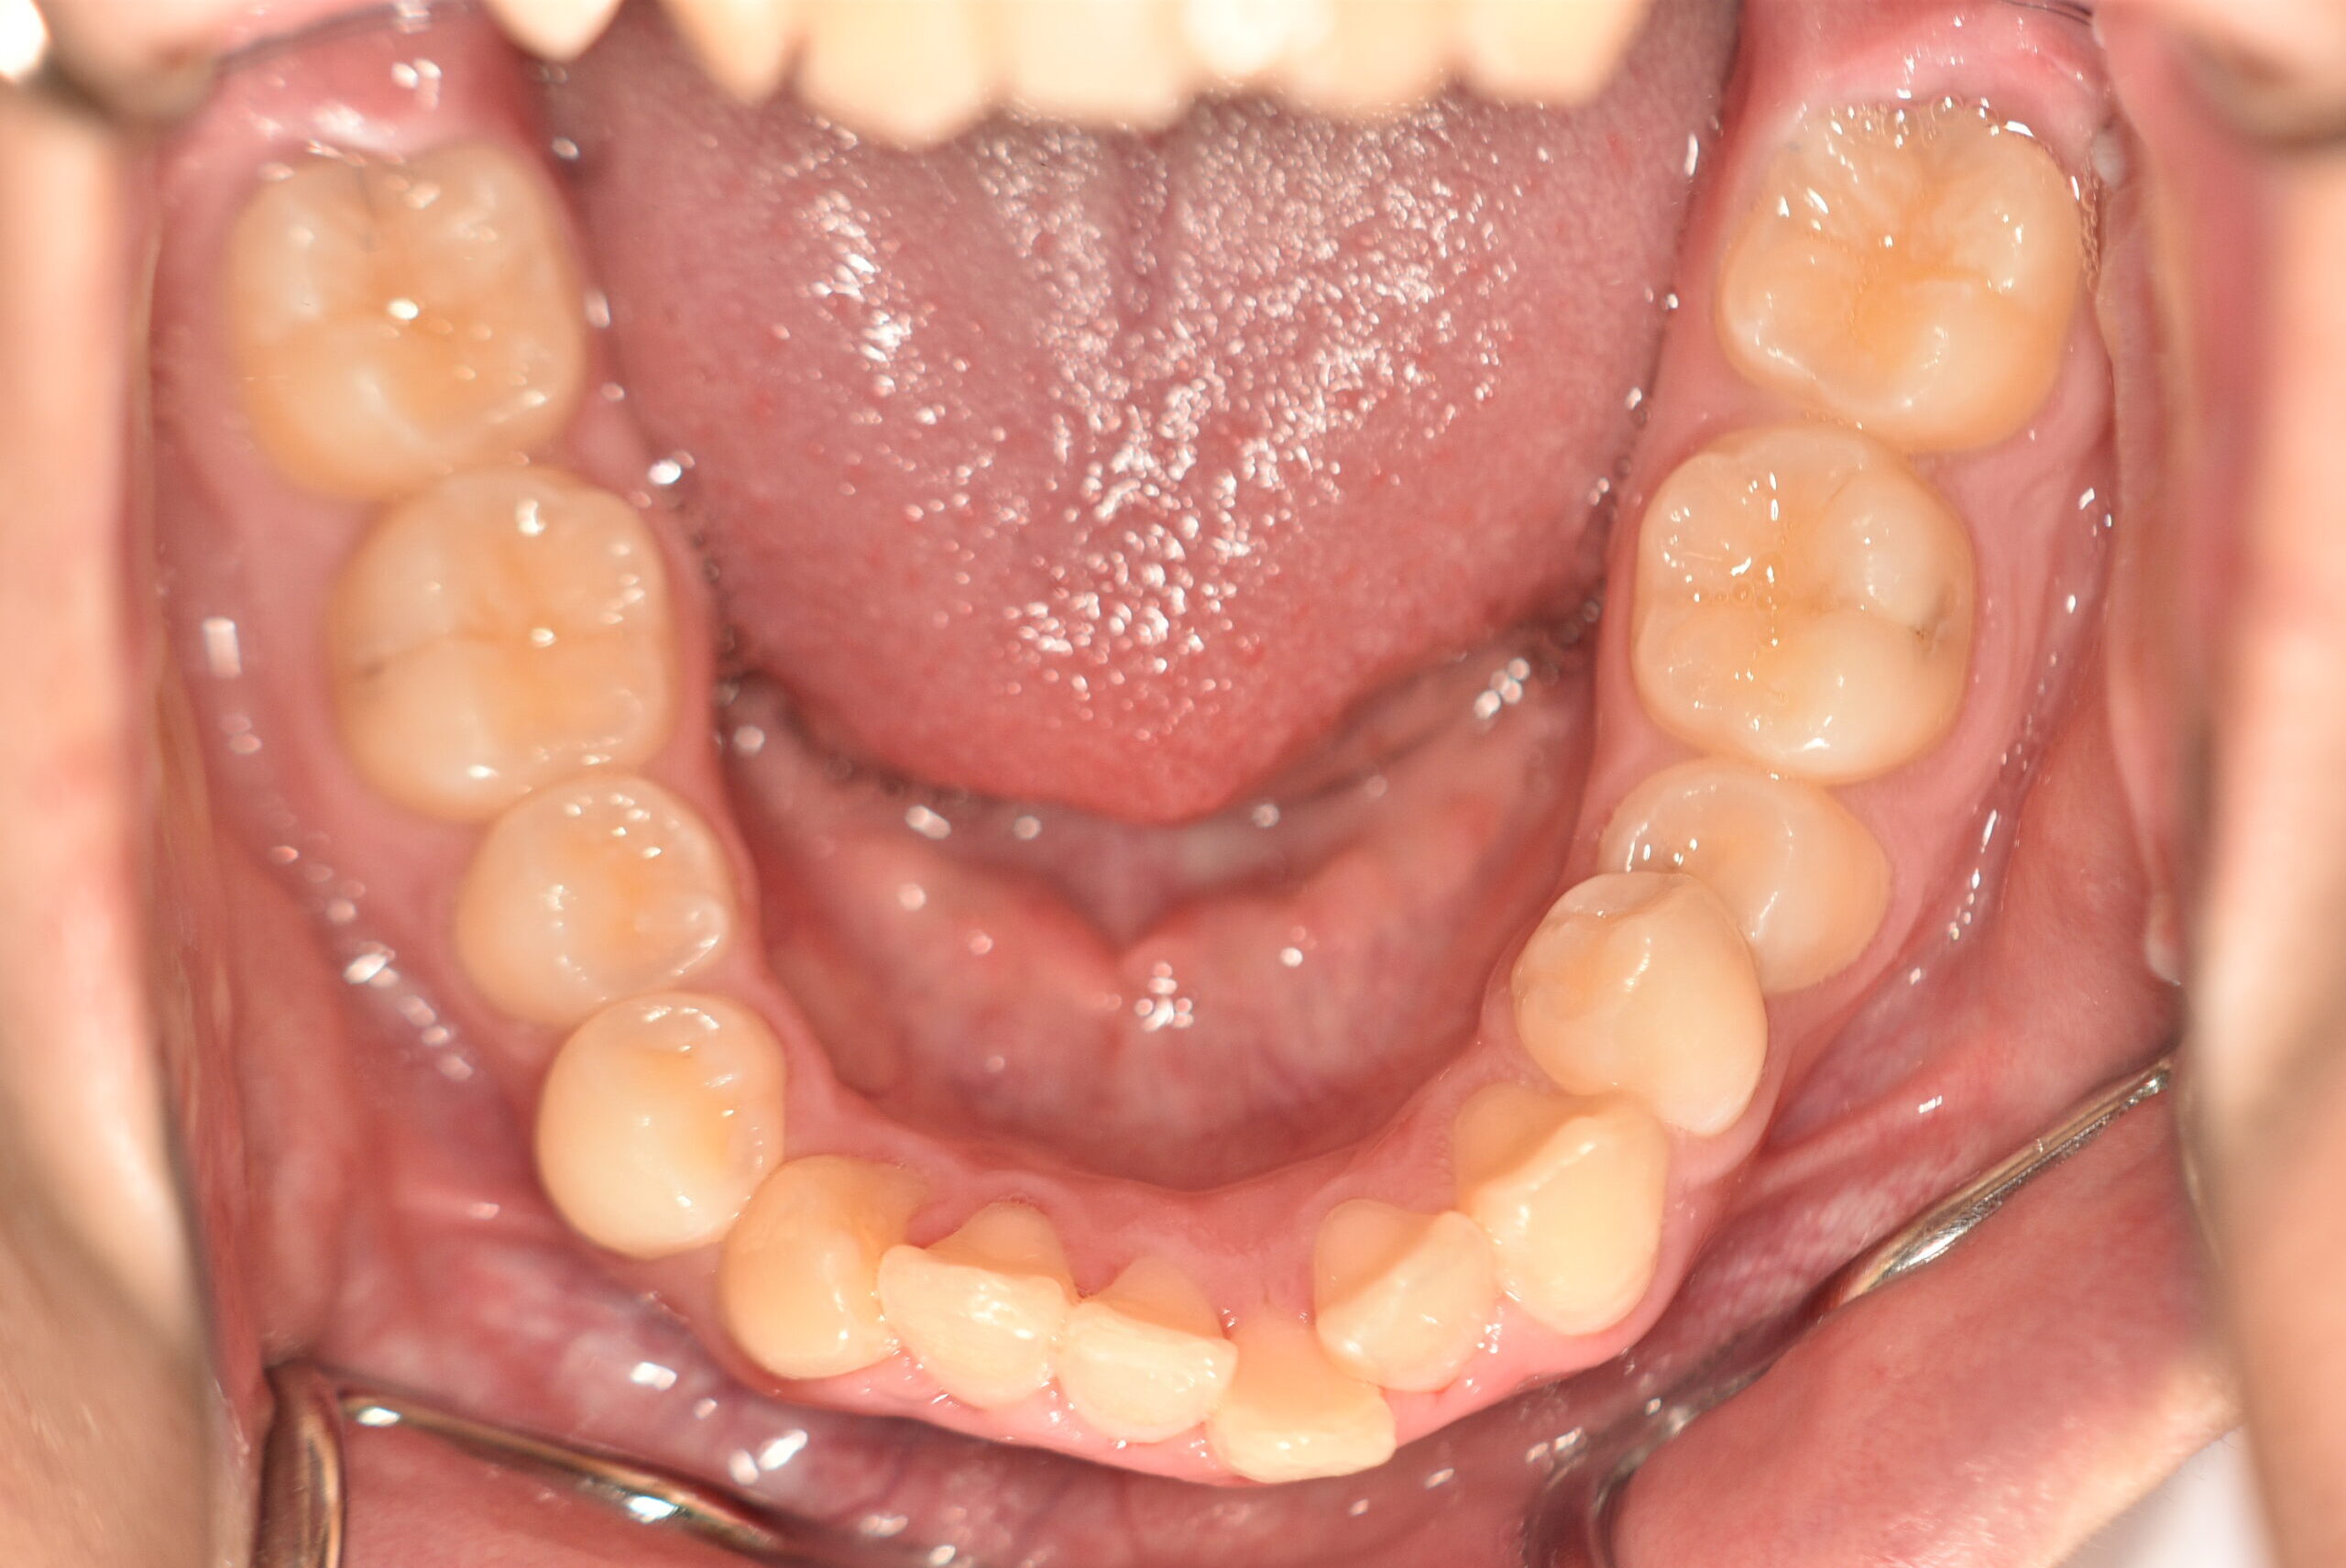

| 治療内容の詳細 | 初診時16歳の男性で、歯のがたつき、かみ合わせを気にされ来院しました。 検査の結果、アングルⅡ級2類不正咬合と診断しました。 治療としては、非抜歯の上、セルフライゲーションブラケット装置(デーモンシステム)で配列を行いました。 同時に顎間ゴムにて咬合関係の改善を行いました。 治療期間は、1年6ヶ月でした。 |